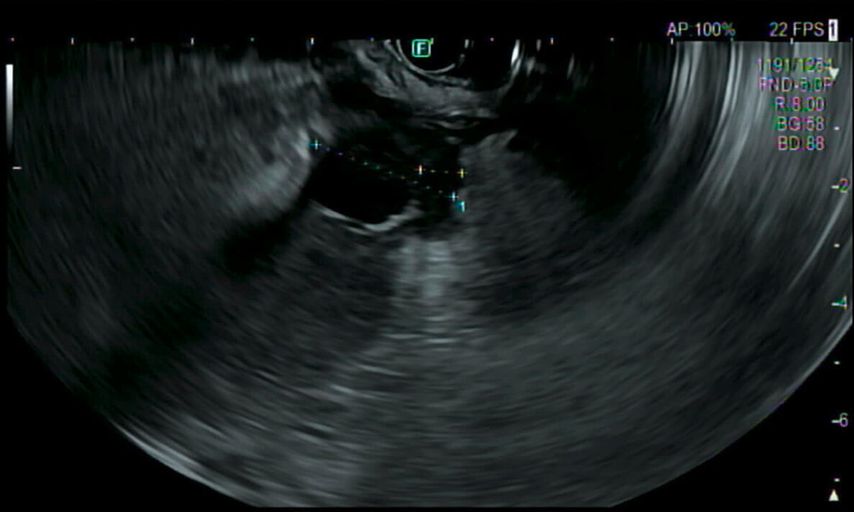

Im Rahmen der Narkose wird eine Sonografie des Abdomens ergänzt, in der sich nun der Verdacht bestätigt, dass die große Fluidokollektion nicht im Magen, sondern intramural in der ventralen Magenwand liegt.

Es folgen eine sonografisch gezielte Punktion und perkutane Pigtail-Drainageanlage in die Fluidokollektion (Abb.3). Prompt entleeren sich 2,8l Pus. Die Drainage wird regelmäßig gespült und für 10 Tage belassen. In der Kultur des Punktats können Streptococcus anginosus und Klebsiella pneumoniae nachgewiesen werden, die initial eingeleitete Antibiose mit Piperacillin/Tazobactam wird antibiogrammgerecht umgestellt. Eine Kontrollgastroskopie (Abb.4) zeigt einen unauffälligen Befund am Pylorus und im Bulbus sowie in der Pars descendens duodeni, zahlreiche Biopsien der Magenschleimhaut ergeben eine geringgradige chronische, inaktive Corpusgastritis mit mukosalem Ödem.